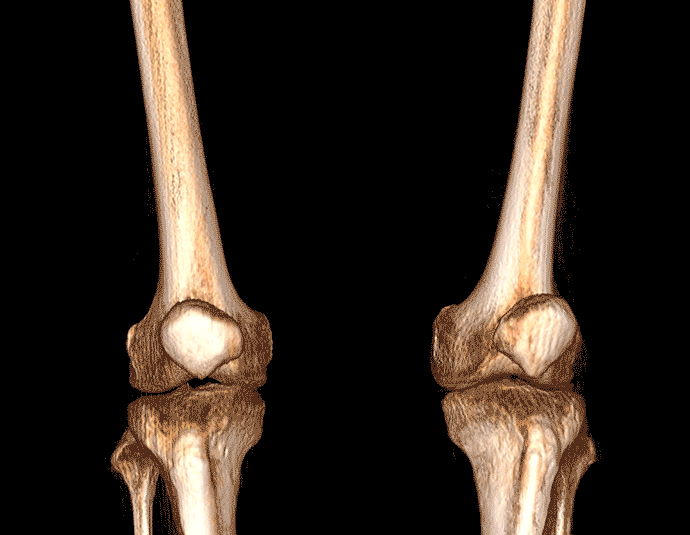

膝關節

VR體繪制重建